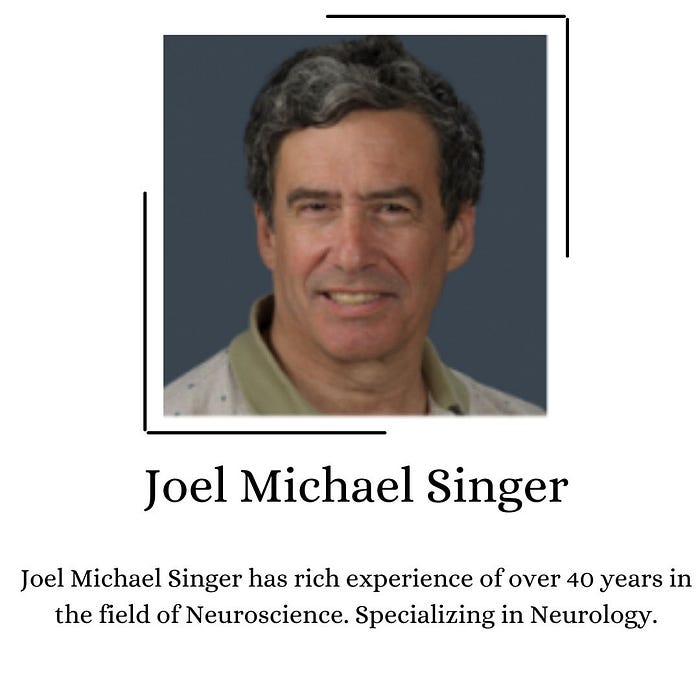

Who is Joel Michael Singer?

Joel Michael Singer is an American neurologist who has served many years in that particular field.